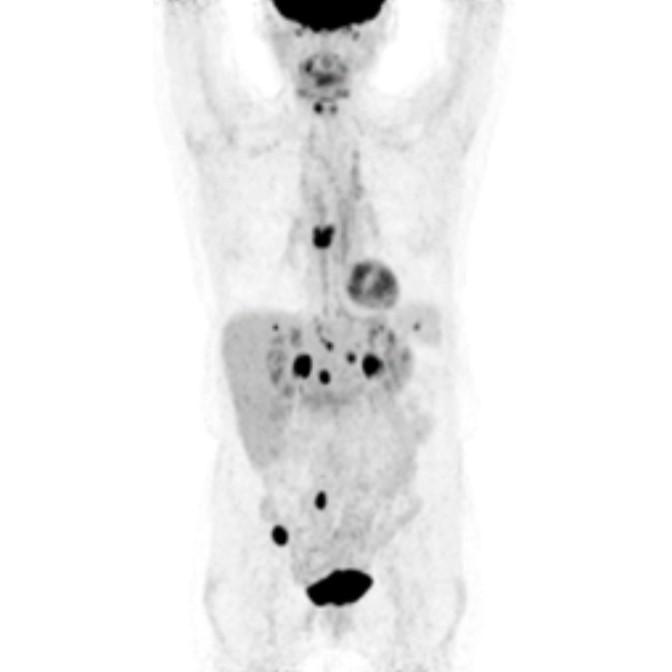

Partial nml and melanoma PET scan

The goal of PET/CT imaging in oncology is to enable the physician to distinguish between benign and malignant pathologies, to determine the extent of disease, to detect residual and recurrent tumors, to monitor the effectiveness of treatments, and to guide therapies.